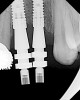

The chief complaint of a 48-year-old woman who presented to her restorative dentist was, “I don’t like the way my implant looks” (Figure 1). This implant had been placed by a previous periodontist and restorative dentist. The patient is now seeking a second opinion. In evaluating this case upon referral to the periodontist, a reddened appearance of the gingival and mucosal tissue encompassing almost the entire facial aspect could be observed. In addition, the radiographs demonstrated a 5-mm diameter implant in place with a deciduous cuspid in the place of No. 11. Deep probing depths were noted around the facial aspect of the implant, and threads could be detected under the tissue.

In evaluating the options, it was decided that the implant placed was too large and that the deciduous cuspid site could be used for a single implant as an abutment for a cantilevered pontic to restore the missing lateral incisor in a more esthetic manner. The goal the treatment was to augment the lateral incisor site in order to bring the facial tissue level more coronal (Figure 2 through Figure 11).